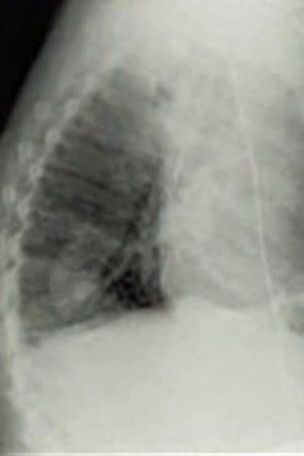

เมื่อวันที่ 12 สิงหาคมที่ผ่านมา สำนักข่าวต่างประเทศรายงานว่า เกิดเรื่องสุดฮือฮาขึ้นในวงการแพทย์ เมื่อนายรอน สวีเดน คุณลุงวัย 75 ปี ได้เข้าพบแพทย์เพื่อขอตรวจมะเร็ง หลังจากรู้สึกว่าตัวเองหายใจไม่ค่อยออกมากว่า 1 เดือน และเมื่อแพทย์ได้เอ็กซ์เรย์ตรวจความผิดปกติของระบบทางเดินหายใจ ก็พบว่ามีถั่วเจริญเติบโตอยู่ในปอดของเขา หาใช่ก้อนมะเร็งร้ายแต่อย่างใด กรณีนี้ก็เลยทำให้บรรดาทีมแพทย์ต่างอึ้งไปตาม ๆ กัน

งานนี้ คุณลุงรอน ได้เปิดเผยว่า ในตอนแรกที่เขารู้สึกเริ่มหายใจติด ๆ ขัด ๆ เขาคิดว่าตัวเองต้องเป็นมะเร็งแน่ ๆ และเตรียมใจรับฟังผลตรวจมาแล้ว แต่เมื่อมาหาหมอแล้วพบว่าจริง ๆ แล้วมีต้นถั่วเจริญเติบโตอยู่ในปอด ก็รู้สึกประหลาดใจมากในตอนแรก เพราะต้นถั่วมีขนาดถึง 1 นิ้วครึ่งเลยทีเดียว แต่ตอนนี้มันกลายเป็นเรื่องน่าตลกสำหรับเขาไปแล้ว และเขาก็โล่งใจมากที่ไม่ได้เป็นมะเร็งอย่างที่ตัวเองคิด

ส่วนทางด้านแพทย์ผู้รักษาคุณลุงรอน ได้กล่าวว่า คุณลุงรอนน่าจะกินเมล็ดถั่วเข้าไป แต่ถั่วเจ้ากรรมกลับไม่ลงไปในกระเพาะอาหาร กลับไปติดอยู่ที่ปอด ความชื้นและอุณหภูมิอุ่น ๆ ในปอด ก็เลยทำให้เมล็ดถั่วเจริญเติบโตเป็นต้นถั่วขึ้นมาได้